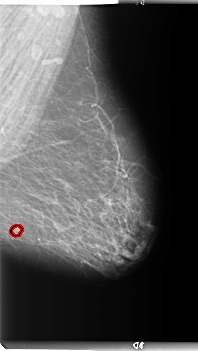

B_3089_1.LEFT_CC

LEFT_CC LINES 5904 PIXELS_PER_LINE 3200 BITS_PER_PIXEL 12 RESOLUTION 50 OVERLAY

FILE: B_3089_1.LEFT_CC.OVERLAY

TOTAL_ABNORMALITIES 1

ABNORMALITY 1

LESION_TYPE MASS SHAPE ROUND MARGINS CIRCUMSCRIBED

ASSESSMENT 4

SUBTLETY 4

PATHOLOGY MALIGNANT

TOTAL_OUTLINES 1

BOUNDARY